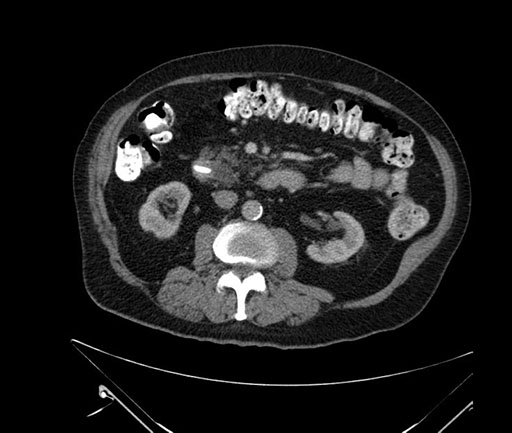

Axial - stented